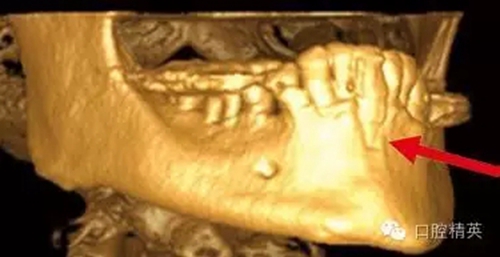

圖7a:6,7號牙種植體(3*15mm)折斷前,從物理學理論上講,種植體骨整合后,基臺螺絲和種植體相連接的支點處是受力時種植體最薄弱的位置。(a)可見6號牙種植體的折斷面,和7號牙種植體上的折裂線(b)

圖7b:6,7號牙種植體折斷后。

圖7c,d:6,7號牙的回顧性模型分析顯示為了獲得滿意的美學效果牙冠不得不做的很長,從而形成較深的咬合關系。同時可見對

頜牙磨耗嚴重,廣泛。

種植體折斷可能發(fā)生于種植體行使功能幾年后,也可能發(fā)生于早期。(圖7a,b)對于圖中這一病例,治療計劃是在對患者的咬合關系,未來修復體理化環(huán)境,患者咀嚼習慣等充分評估后制定的。種植體折斷后,對該病例進行了回顧性病因分析,上了頜架的模型揭示了過長的頜間距離,和嚴重、廣泛的對頜牙磨耗(圖7c,d)。對于這一病例,醫(yī)生仔細評估了所有可得到的回顧性診斷信息,和患者進一步討論交流后,提出了幾個診斷建議和一個過渡性治療方案,其中包括將固定修復改為鑄造可摘局部義齒。